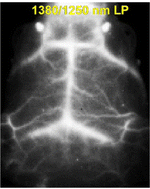

The use of conjugated polymer nanoparticles in biological imaging is emerging as an effective method of analysis and diagnosis, with their enhanced optical stability and wide colour pallete a distinct advantage over existing dye systems. Notably, the wide range of materials available include narrow band gap polymers, not originally designed for imaging but with fortuitous electronic properties that can be exploited in clearly defined near-infrared regions, areas of great interest to clinicians and biologists as transparent windows. Traditionally, few materials can be used as convenient probes in the near infrared, however, conjugated polymers provide an immediate solution to imaging in this desirable spectral range.